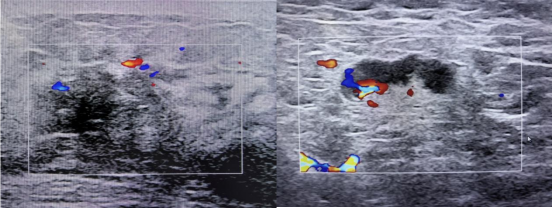

2023年10月14日 乳腺彩超

左侧低回声区,建议完善相关检查,BI-RADS 4A类

左腋下淋巴结肿大

图1 双侧乳腺及双腋下锁骨上下彩超